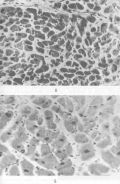

Рис. 4. Поперечный срез волокон нормального миокарда — А, компенсаторная гипертрофия миокарда при гипертонической болезни — Б (по Д. С. Саркисову) |

При заболеваниях, приводящих к снижению функции органа (например, при пороке сердца), развивается гипертрофия, обозначаемая как компенсаторная (рис. 4). Она обычно длительное время поддерживает нарушенную функцию на нормальном или близком к нему уровне, способствует продлению жизни больного. Вместе с тем со временем происходит истощение функциональных возможностей гипертрофированной ткани органа, развивается его функциональная недостаточность со всеми вытекающими отсюда последствиями. Современная хирургия уже на ранних стадиях этого процесса предпринимает все более успешные попытки заменить больной орган на здоровый. Проблема трансплантации органов, как уже говорилось (см. П.4.1), осложнена активностью иммунной системы, которая способствует отторжению чужеродного биологического объекта.